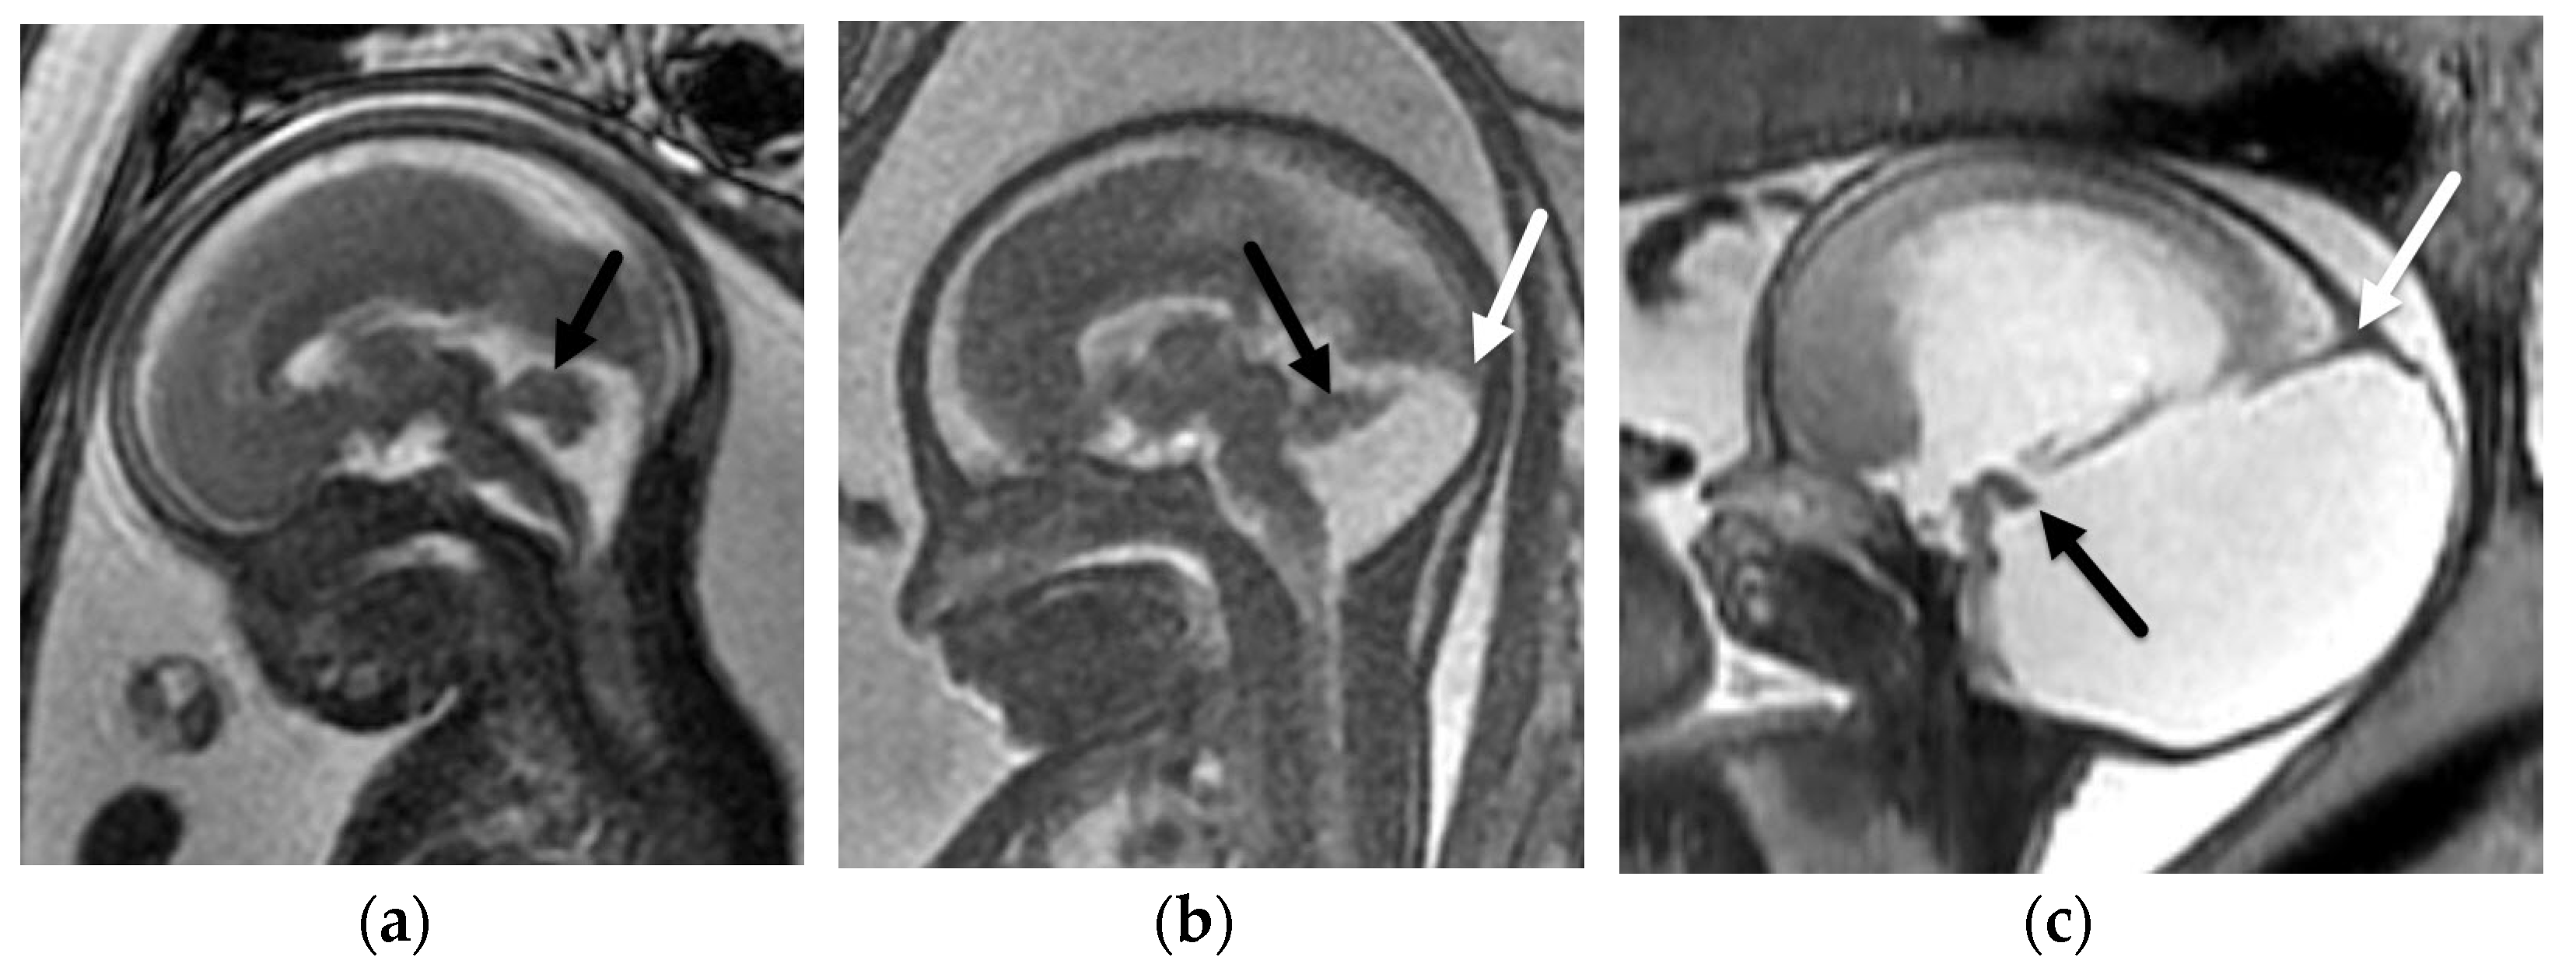

5.1. Dandy-Walker Continuum

- Venkatesan, C.; Kline-Fath, B.; Horn, P.S.; Poisson, K.E.; Hopkin, R.; Nagaraj, U.D. Short- and Long-Term Outcomes of Prenatally Diagnosed Dandy-Walker Malformation, Vermian Hypoplasia, and Blake Pouch Cyst. J. Child Neurol. 2021, 36, 1111–1119. [Google Scholar] [CrossRef]

- Kollias, S.S.; Ball, W.S.; Prenger, E.C. Cystic malformations of the posterior fossa: Differential diagnosis clarified through embryologic analysis. Radiographics 1993, 13, 1211–1231. [Google Scholar] [CrossRef]

- Nagaraj, U.D.; Kline-Fath, B.M.; Horn, P.S.; Venkatesan, C. Evaluation of Posterior Fossa Biometric Measurements on Fetal MRI in the Evaluation of Dandy-Walker Continuum. AJNR Am. J. Neuroradiol. 2021, 42, 1716–1721. [Google Scholar] [CrossRef] [PubMed]

- Robinson, A.J.; Ederies, M.A. Seminars in Fetal & Neonatal Medicine Diagnostic imaging of posterior fossa anomalies in the fetus. Semin. Fetal Neonatal Med. 2016, 21, 312–320. [Google Scholar] [PubMed]

- Nagaraj, U.D.; Kline-Fath, B.M.; Calvo-Garcia, M.A.; Vadivelu, S.; Venkatesan, C. Fetal and postnatal MRI findings of Blake pouch remnant causing obstructive hydrocephalus. Radiol. Case Rep. 2020, 15, 2535–2539. [Google Scholar] [CrossRef]